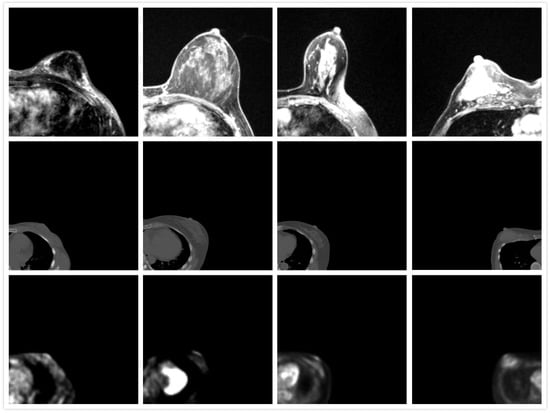

3.1. Model Performance

3.2. Registration Error